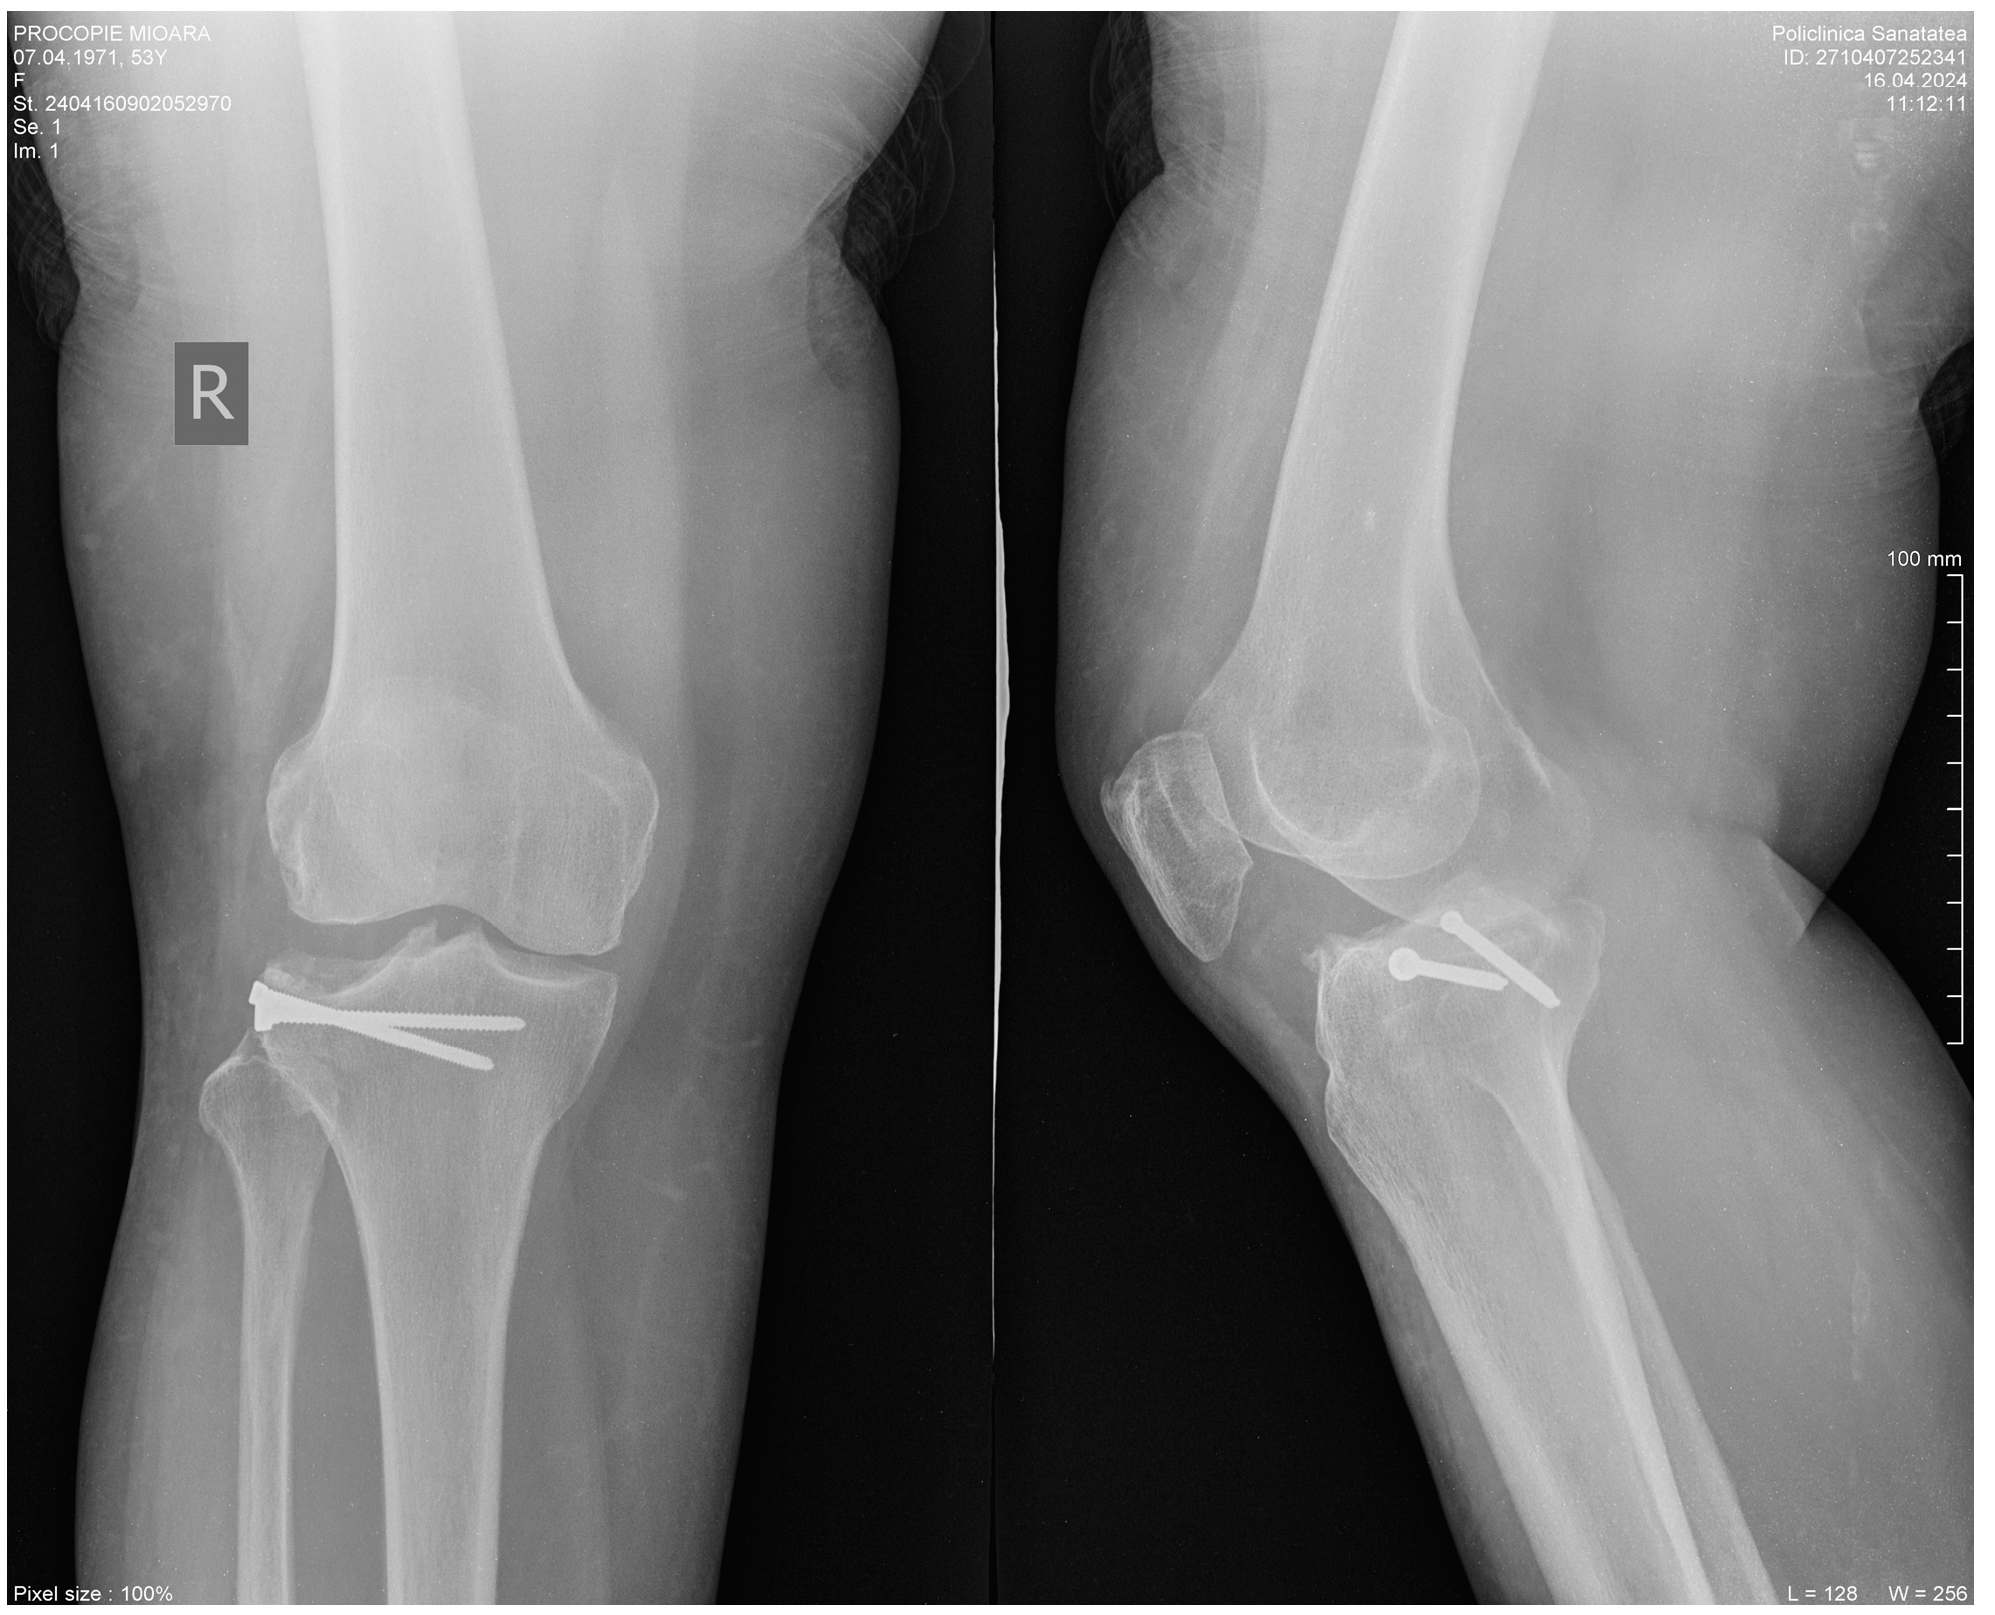

Sticky Bone as a New Type of Autologous Bone Grafting in Schatzker Type II Tibial Plateau Fracture Case Report

2. Clinical Case Presentation